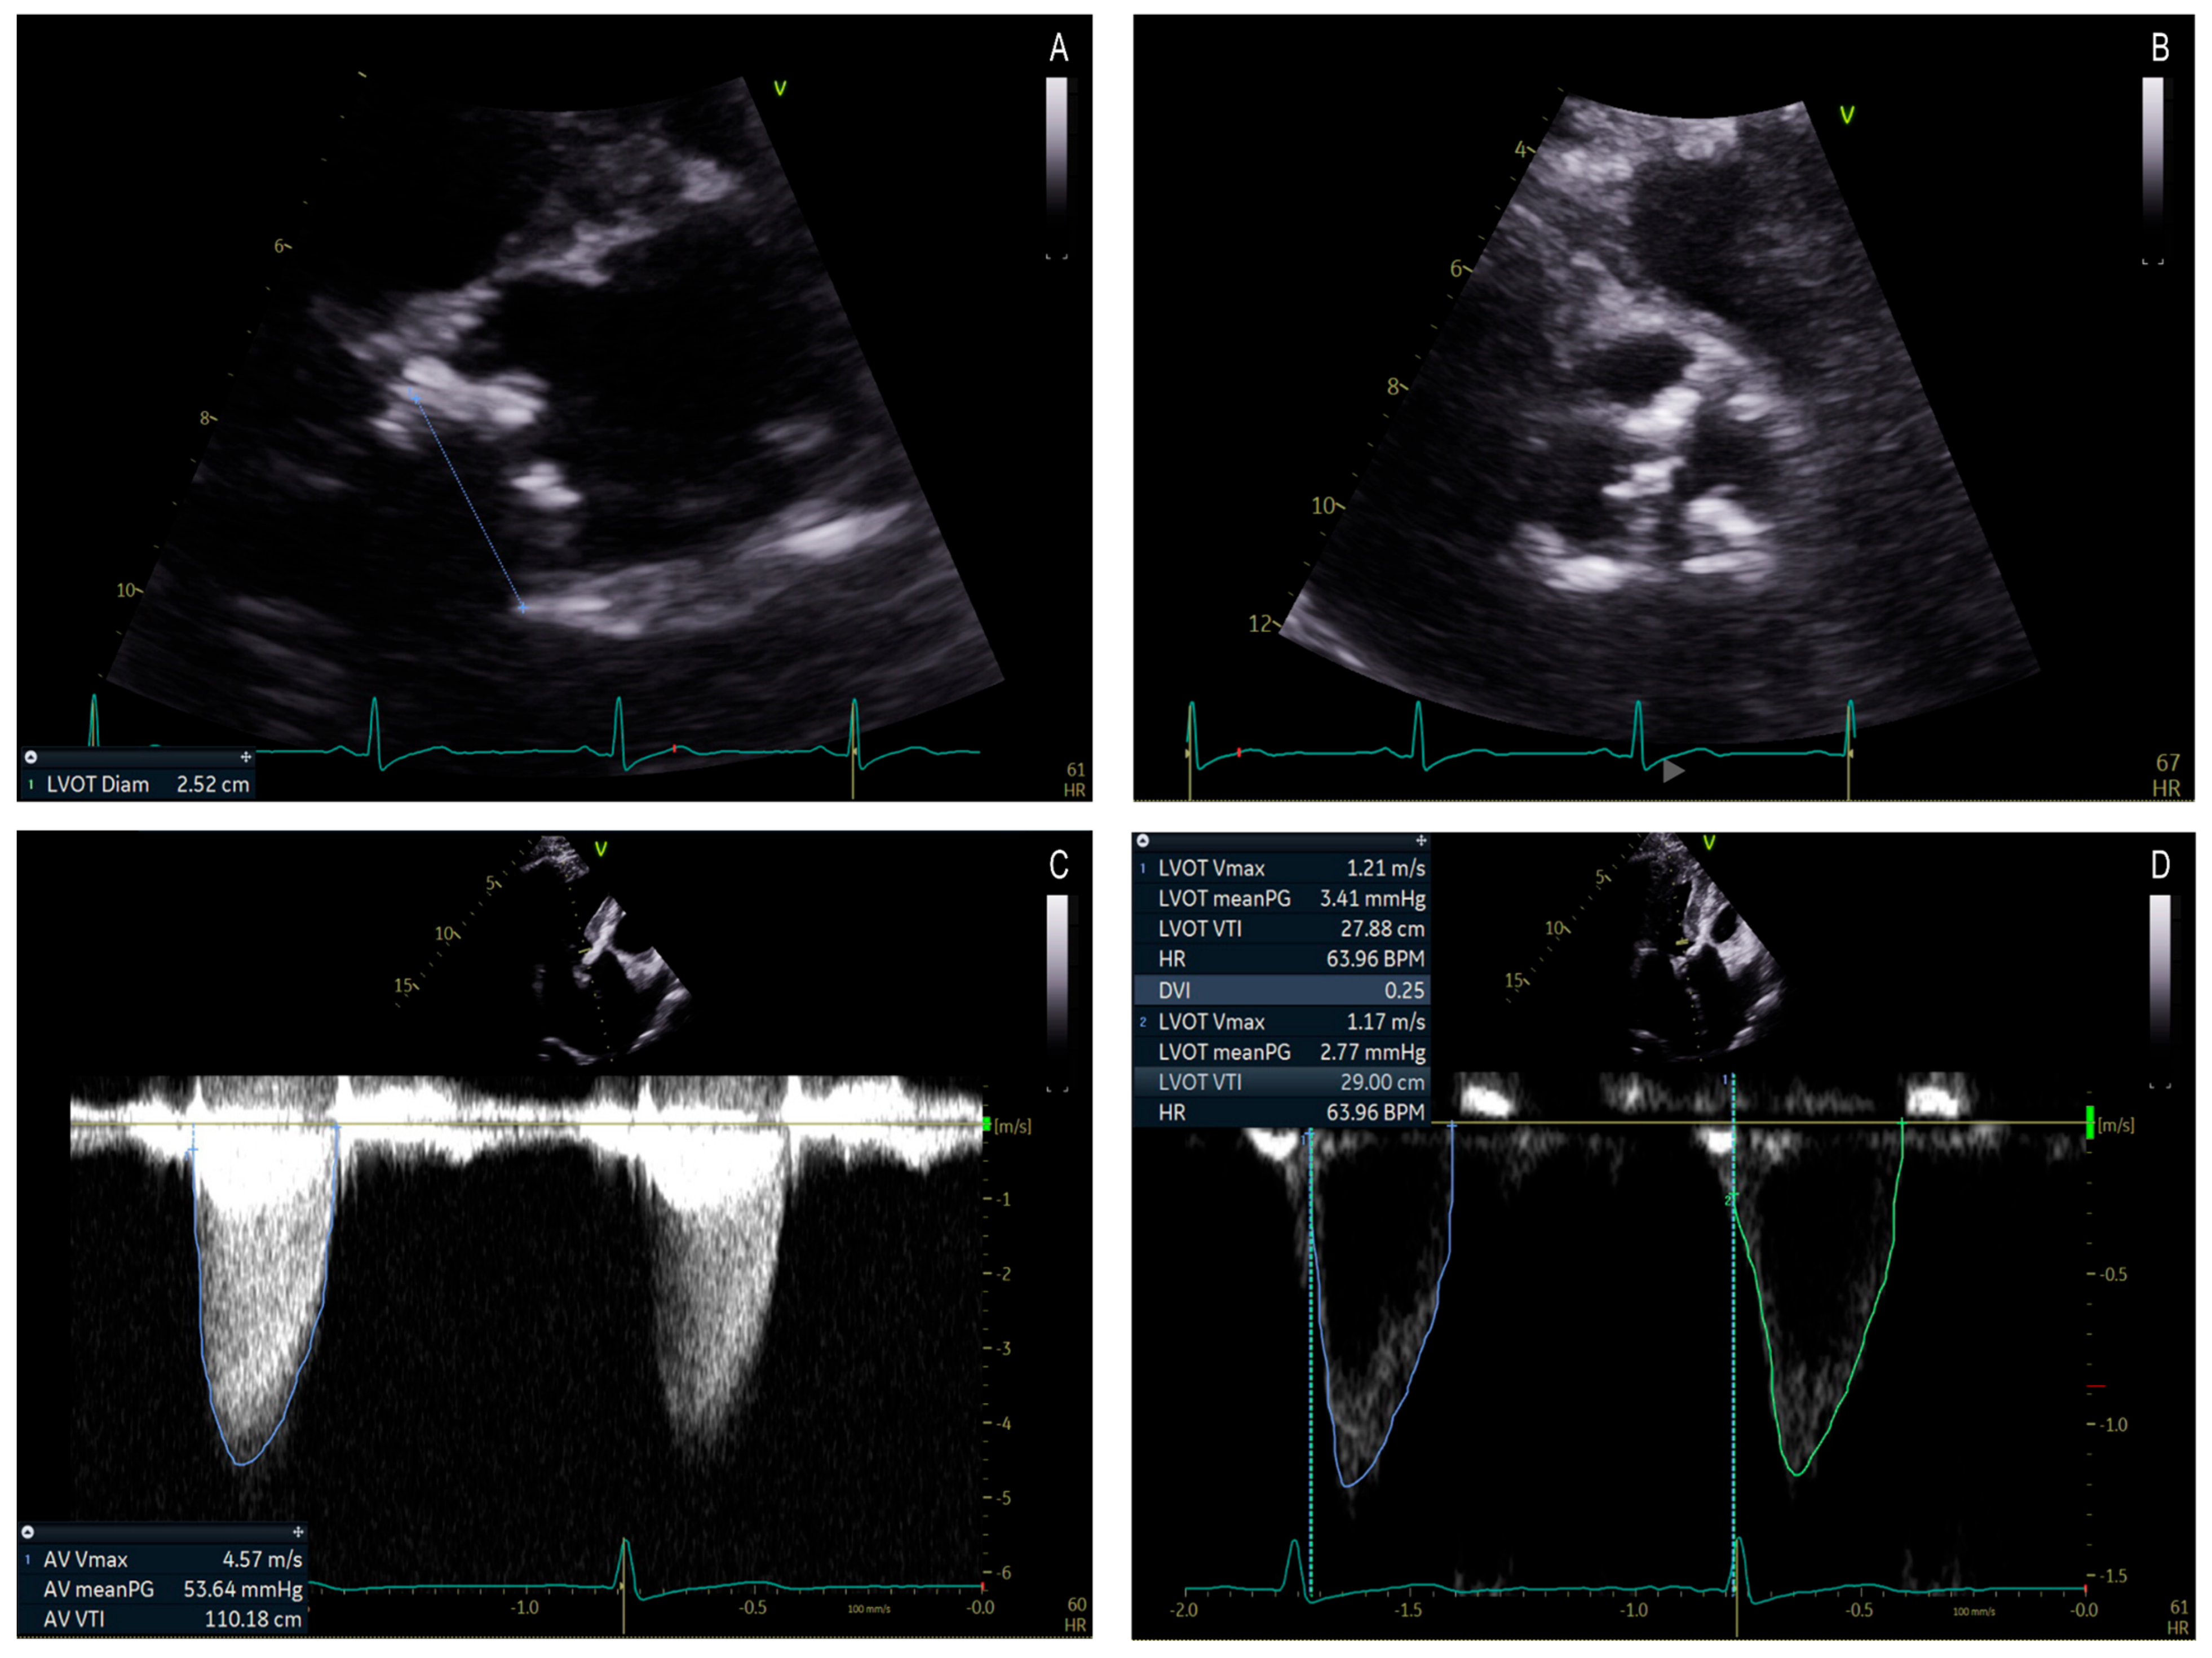

Accurate measurement of the AVA using planimetry can be a useful tool in patients with DHG-AS (Table 3). Although planimetry is less effective with 2D TTE due to extensive valve calcification and imaging plane that may not be aligned with level of the smallest valve orifice, 3D TTE, transesophageal echocardiography (TEE), or multislice computed tomography (MSCT) 3D planimetry can provide more accurate anatomic measurements of the AVA (Figure 5) [26,32,33,34]. Multiple studies have validated the clinical and prognostic relevance of anatomic planimetric aortic valve area assessment in severe AS using TEE, CT, and cardiovascular magnetic resonance imaging (CMR) (Table 4).

Figure 5. Representative examples illustrating the anatomic area obtained by planimetry in different patients with severe aortic stenosis: TEE (0.8 cm2, (A)), CT (0.6 cm2, (B)), and MRI (0.8 cm2, (C)).